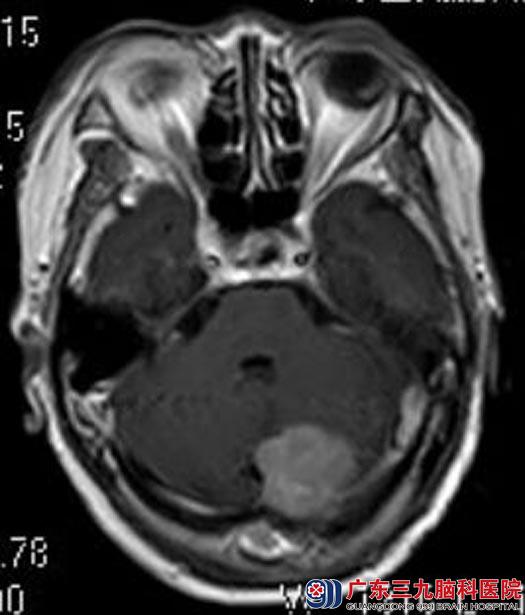

江奶奶已是古稀之年,两周前出现头痛、头晕,休息后好转,未予重视。三天前头痛、头晕较前加重,在儿孙的陪伴下在当地医院行头颅CT检查提示小脑幕占位性病变。广东三九脑科医院神经头颅MR进一步检查提示:小脑幕左侧跨幕上下脑膜瘤,大小约32.3mm×31.0mm×39.7mm,考虑脑膜瘤可能性大。

▲手术前